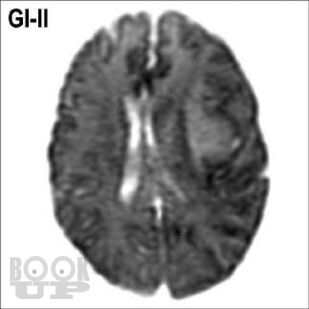

Книга «Опухоли мозга. КТ- и МРТ-диагностика» посвящена диагностике опухолевого поражения центральной нервной системы. При этом широко раскрыты особенности морфологической структуры каждой конкретной опухоли головного мозга. Структура изложения материала основана на классификации опухолей головного мозга по рекомендациям ВОЗ. Представленные опухоли в заголовке содержат шифр МКБ/О из 10-го пересмотра. Под каждым диагностическим изображением имеется подпись с обозначением его характеристик: метод исследования (КТ, МРТ, рентген, ПЭТ и др.), название ширины окна для КТ или импульсной последовательности на МРТ, а также ориентация среза в пространстве (аксиальный, сагиттальный или корональный). Данная особенность позволяет улучшить восприятие изображений, а также избежать путаницы при сопоставлении разных импульсных последовательностей и окон на МРТ и КТ.